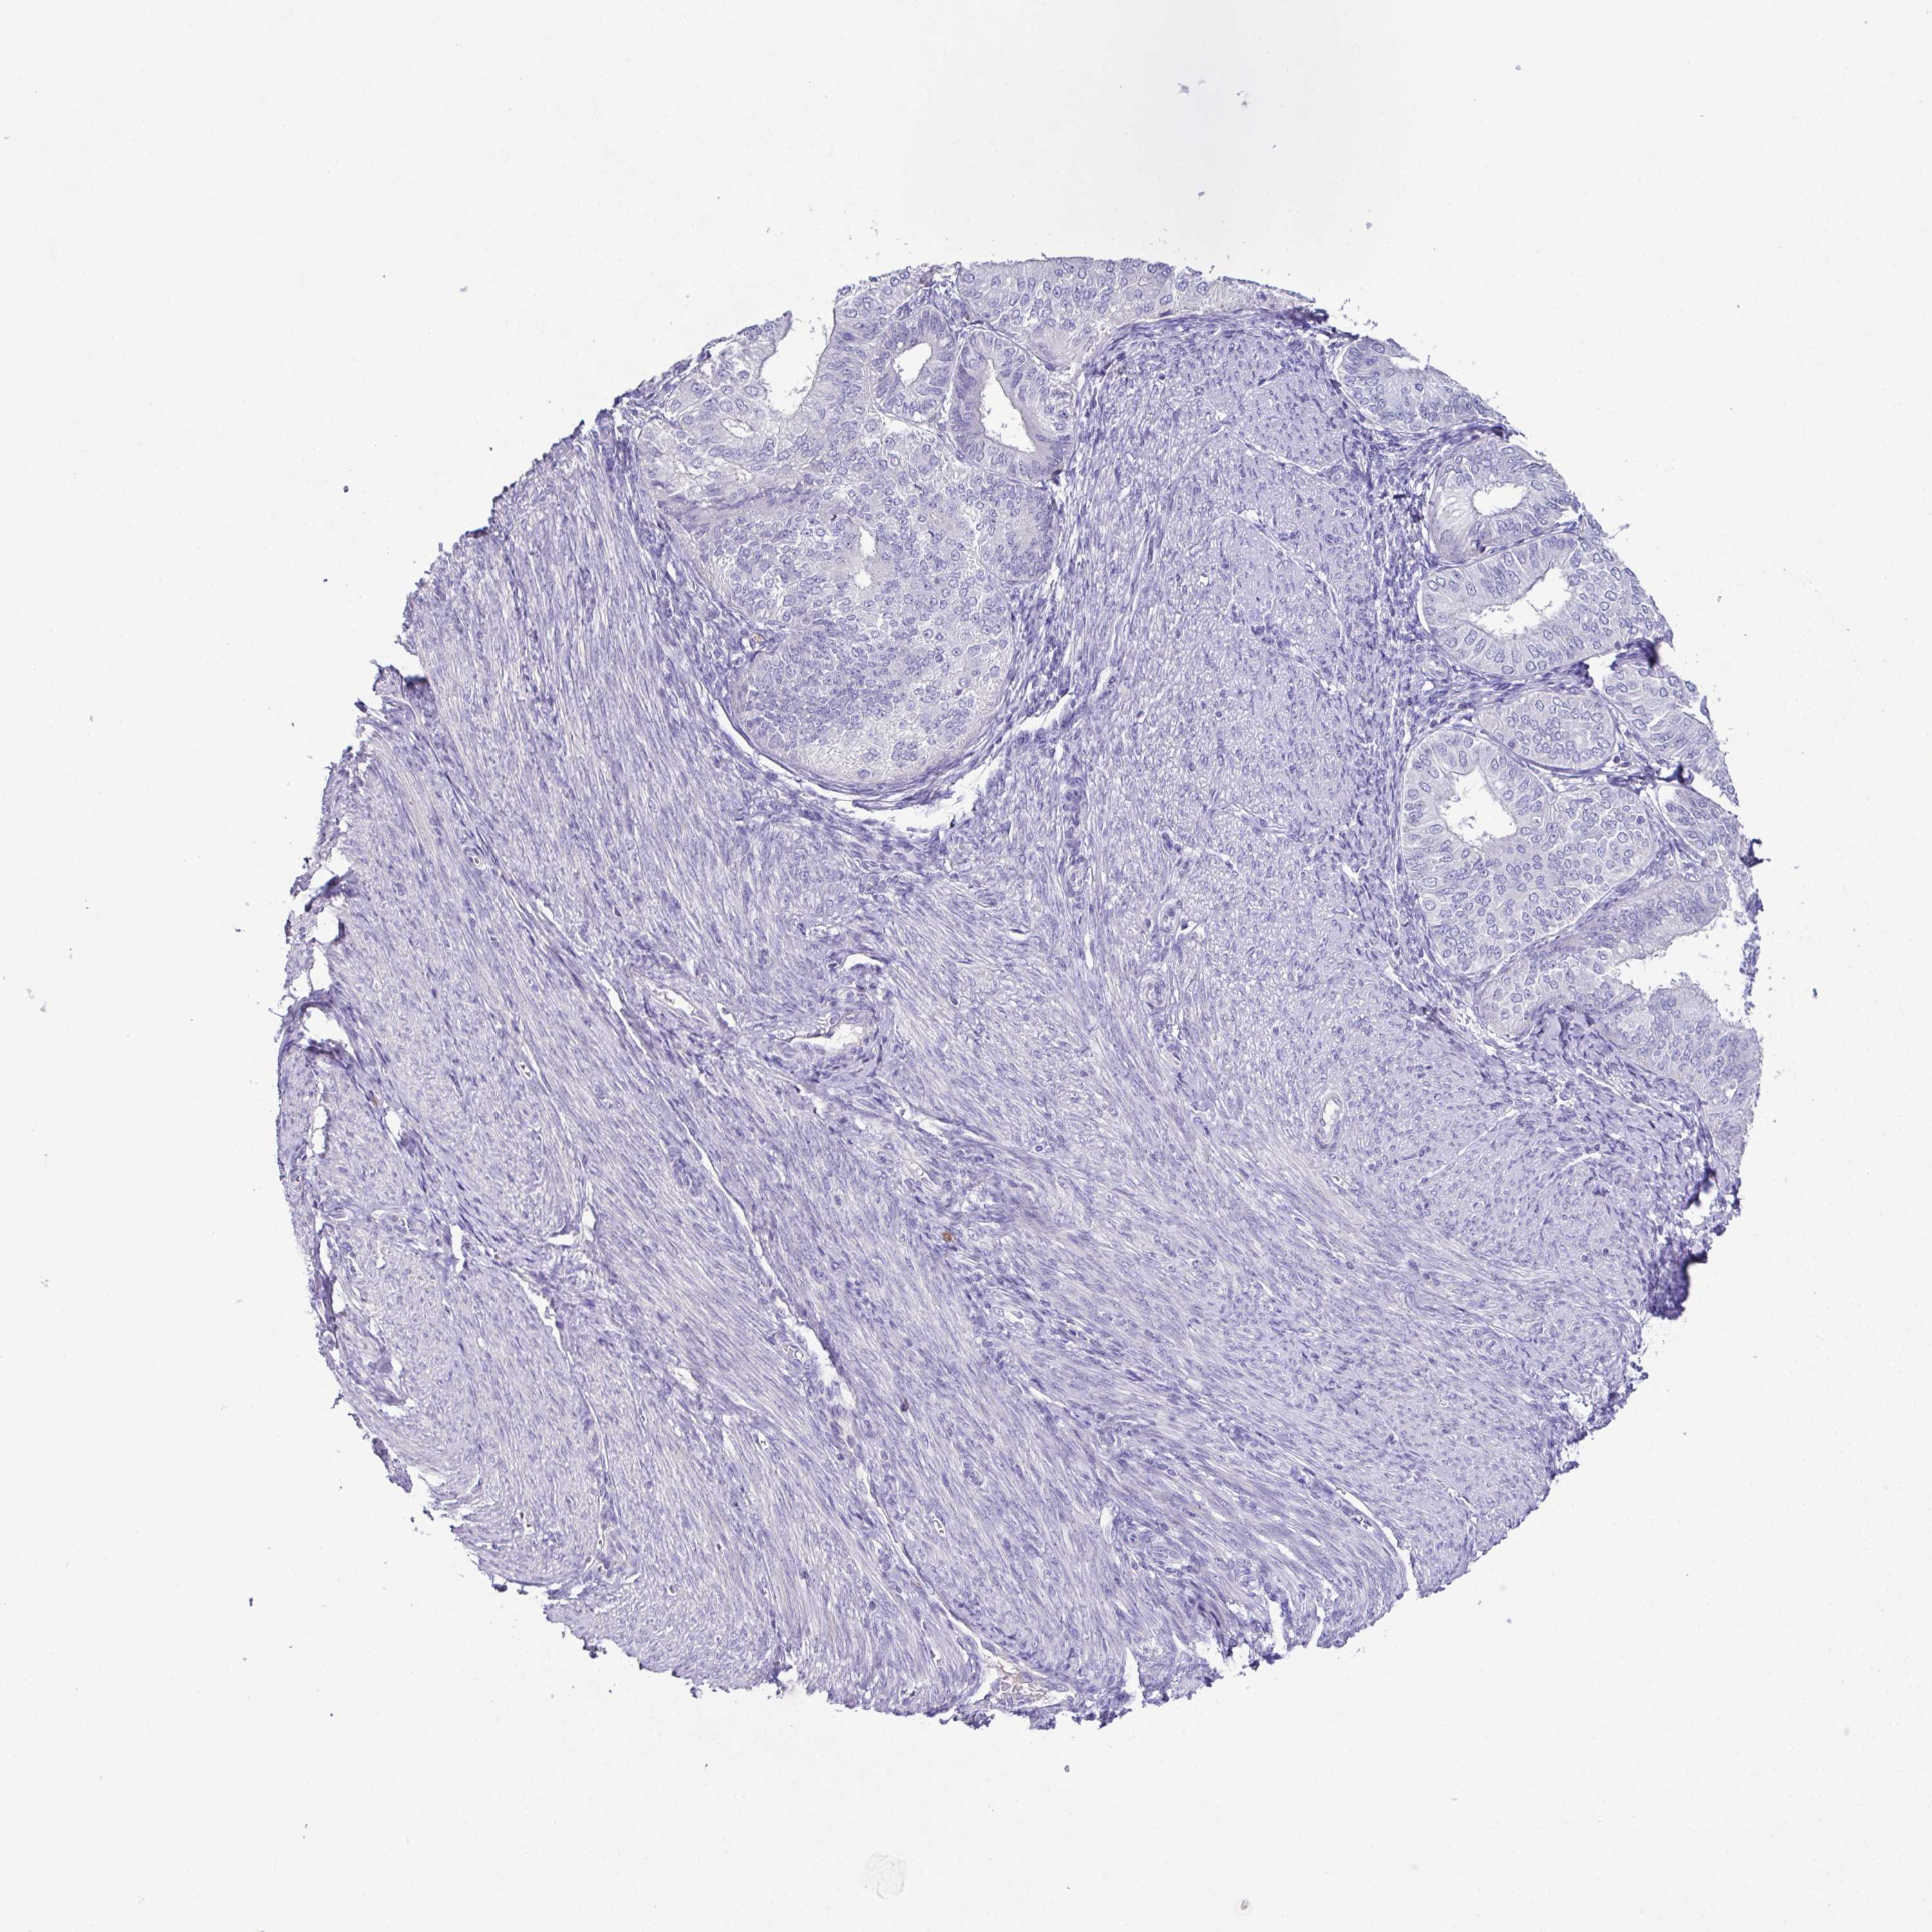

ENDOMETRIAL CANCER - Protein expressioni

A mouse-over function shows sample information and annotation data. Click on an image to view it in a full screen mode. Samples can be filtered based on level of antibody staining by selecting one or several of the following categories: high, medium, low and not detected. The assay and annotation is described here.

Note that samples used for immunohistochemistry by the Human Protein Atlas do not correspond to samples in the TCGA dataset.

Antibody stainingi

Antibody staining in the annotated cell types in the current human tissue is reported as not detected, low, medium, or high, based on conventional immunohistochemistry profiling in selected tissues. This score is based on the combination of the staining intensity and fraction of stained cells.

Each image is clickable and will lead to virtual microscopy that enables deeper exploration of all samples and also displays staining intensity scores, fraction scores and subcellular localization as well as patient and tissue information for each sample.

Antibody HPA063793

Staining

High

Medium

Low

Not detected

Intensity

Strong

Moderate

Weak

Negative

Quantity

>75%

75%-25%

<25%

None

Location

Nuclear

Cytoplasmic/membranous

Cytoplasmic/membranous,nuclear

Adenocarcinoma, NOS

Carcinoma, NOS

Adenocarcinoma, metastatic, NOS